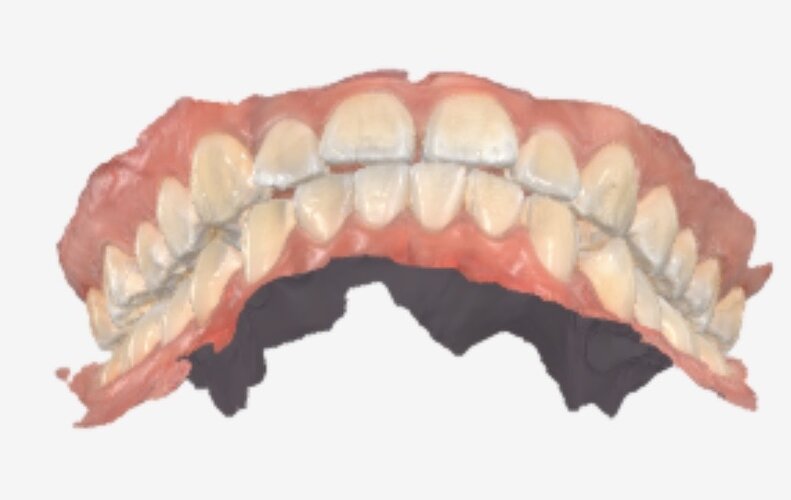

I have a 9mm overbite and ive went to 3 places (2 dentists and one ortho) and theyve all reccomended i pull teeth due to the large overbite and the ortho said that using a palette expander would not give me the space i need to fit my teeth

Must i really pull teeth with such a severe overbite or is there another solution to fix my teeth without risking ruining my side profile

(Ive attached 3 angles of 3d scans of my teeth more can be provided if asked)

Must i really pull teeth with such a severe overbite or is there another solution to fix my teeth without risking ruining my side profile

(Ive attached 3 angles of 3d scans of my teeth more can be provided if asked)